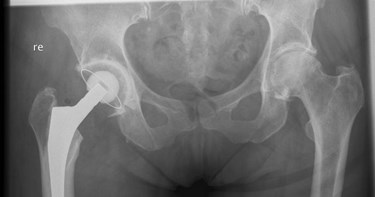

Een heupprothese bestaat doorgaans uit drie onderdelen: een steel, een kop en een kom. De steel met daarop de kop zit in het bovenbeen en kan bewegen in de kom die in het bekken zit.